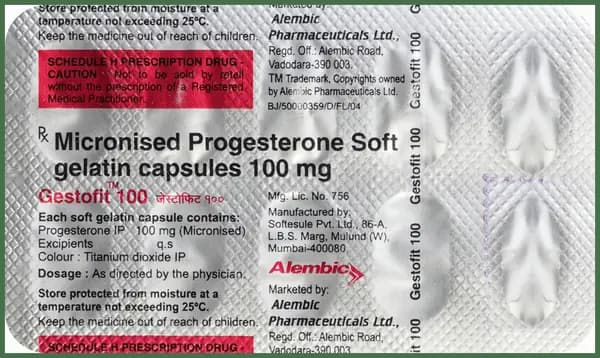

Gestmarck 400 Soft Gelatin Capsule

Bismarck Pharmaceuticals Pvt. Ltd.

Composition

Progesterone (Natural Micronized)400mg

₹475₹594

Get Substitute at 89% Cheaper

89%

Composition

Progesterone (Natural Micronized)400mg

Rx Required

Get Substitute at 89% Cheaper

89%

Gestmarck 400 Soft Gelatin Capsule

Bismarck Pharmaceuticals Pvt. Ltd.

₹

475594